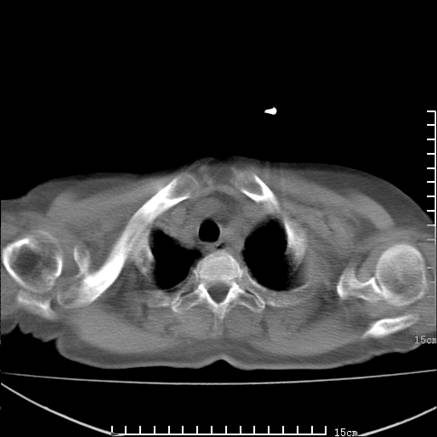

女,王某,58岁,咳嗽三个月余,基层医院二个月前诊为肺结核,用抗结核药二个月无明显疗效。

心包积液致肺瘀血.右侧周围型肺癌伴肺内转移,中间裂积液,叶间胸膜肥厚.右上肺大泡,右侧胸膜肥厚.

双肺继发型tb,心功能不全并肺淤血、心包、双侧叶间裂积液,肺大泡,右下胸膜肥厚钙化。